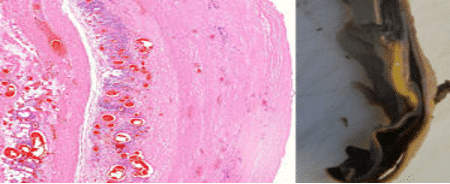

Pragu aordi seinas, mida ääristavad lümfotsüütide kobarad, mis põhjustab aordi rebendi

Vasakul lõik läbi aordi seina. See pilt on tehtud veelgi väiksema suurendusega kui eelmine; lümfotsüüdid paistavad nüüd vaid pisikeste siniste täppide pilvena. Sellest sinisest pilvest vasakul näeme vertikaalset pragu, mis läbib koe. Selline pragu on makroskoopiliselt nähtav ka paremal näidatud aordi väljalõigatud proovis.

Aort on keha suurim veresoon. See võtab vastu südame vasakust vatsakesest väljutatud kõrge rõhu all olevat verd ja puutub seega kokku tugeva mehaanilise stressiga. Kui aordi sein on põletiku tõttu nõrgenenud, nagu on see siin, võib see praguneda ja puruneda. Aordirebend on tavaliselt üsna haruldane, kuid prof Burkhardt leidis oma piiratud arvul lahkamistel mitmeid juhtumeid. Samuti näidati, et mõned mõjutatud aordid ekspresseerisid piigivalku.